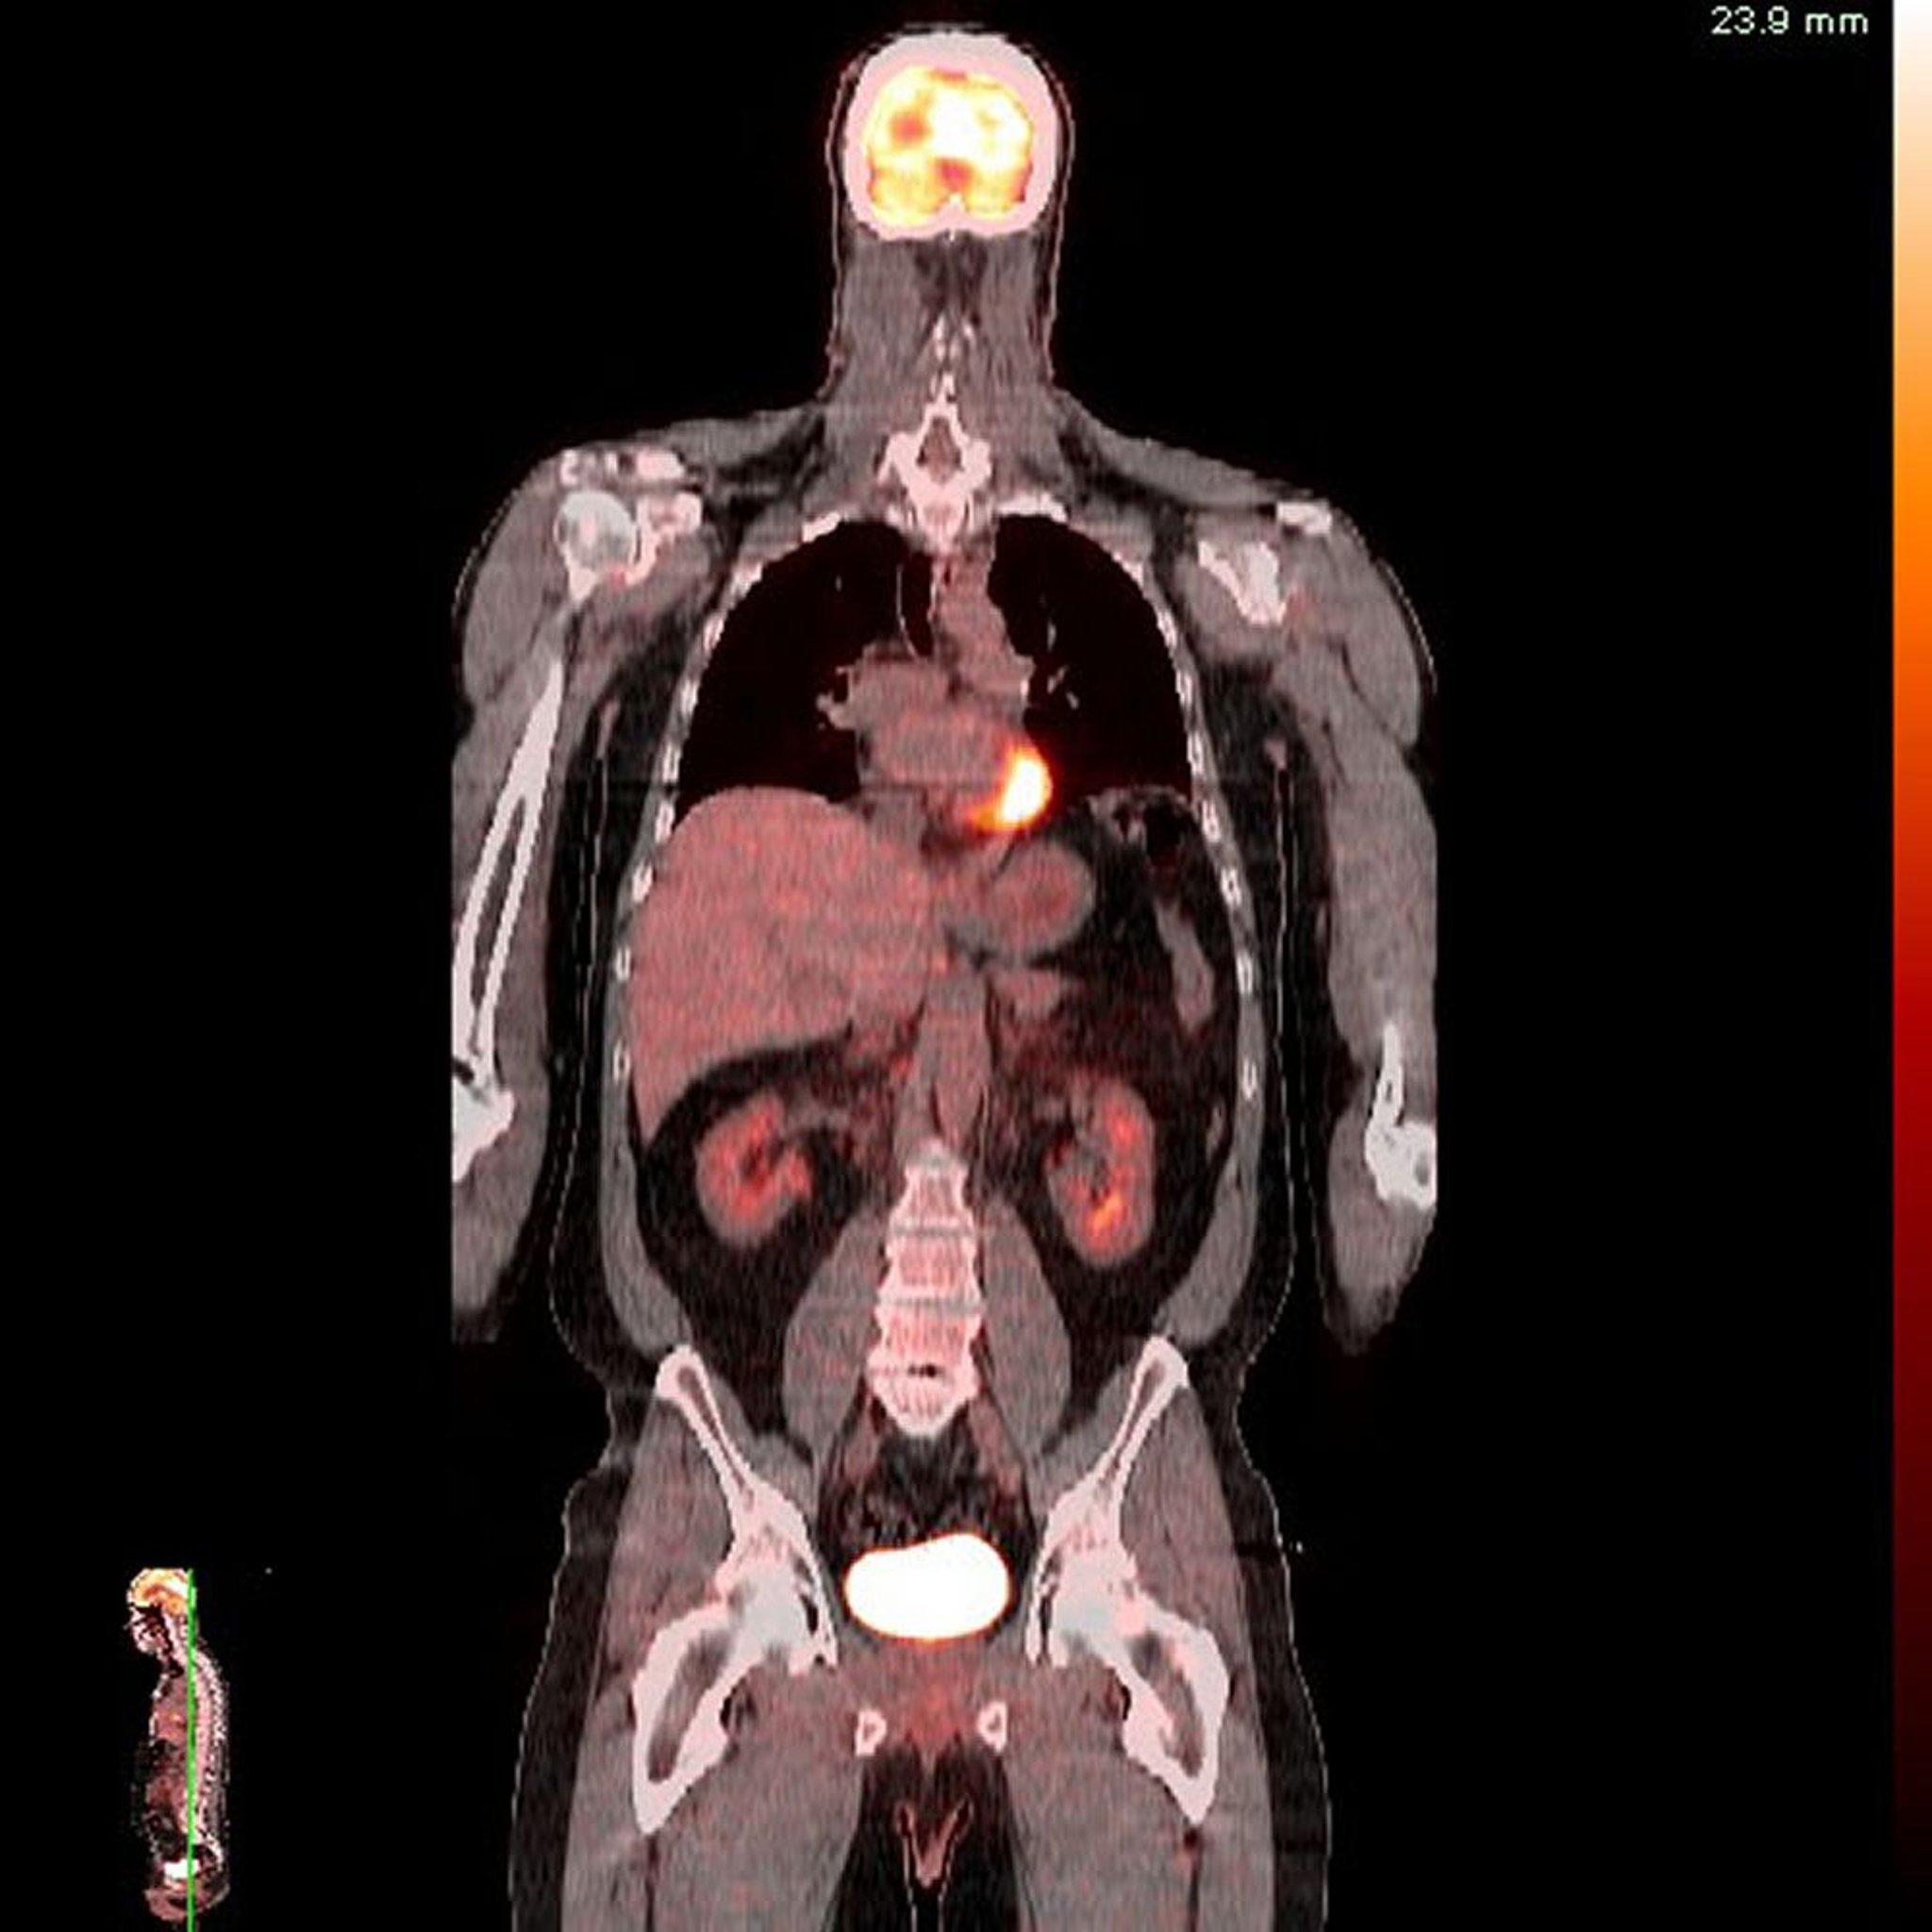

PET-CT検査

Image provided by Jon A.Jacobson, MD.